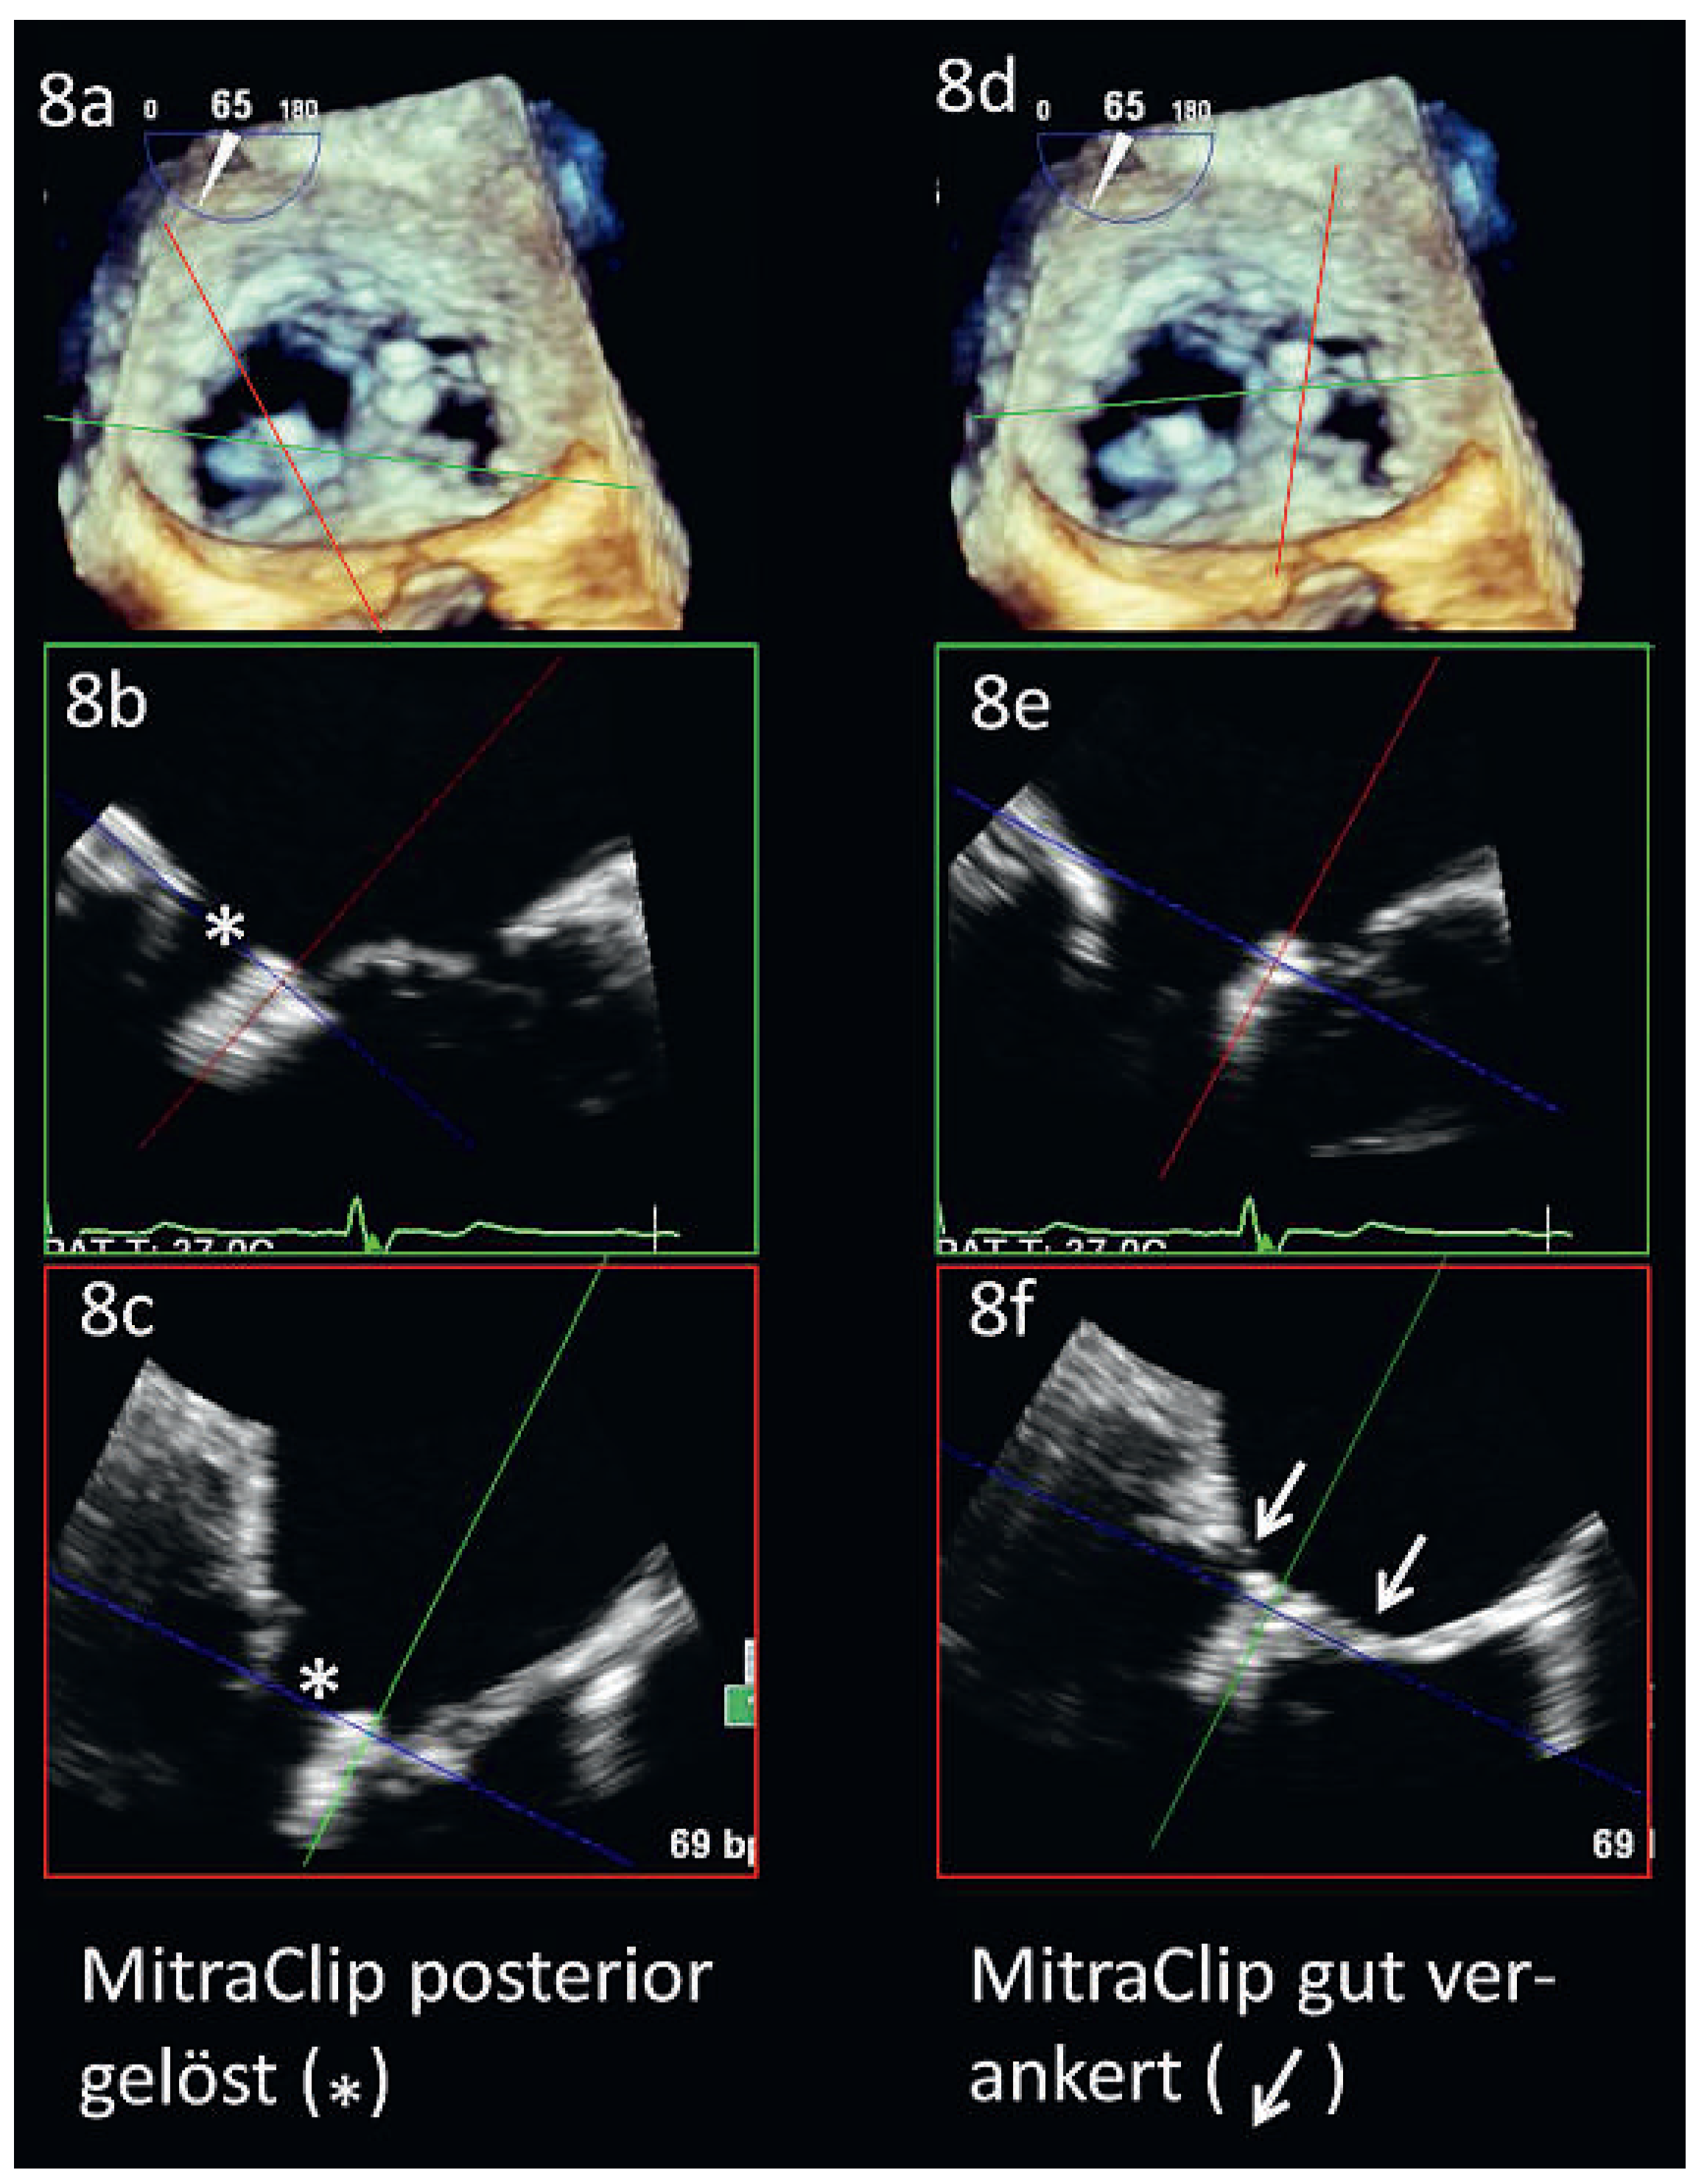

Einer der grössten Vorteile der TEE liegt aber zweifelsohne darin, dass sie nicht nur zur Basisdiagnostik, sondern auch perioperativ zur Beurteilung des Resultates einer Mitralklappenoperation oder-intervention eingesetzt werden kann. Im Falle der perkutanen Mitralklappenrekonstruktion mittels MitraClip ist sie sogar unabdingbare Voraussetzung für eine erfolgreiche Behandlung (Abbildung 8).

Abbildung 8. MitraClip: Erfolgskontrolle mittels 3D-TEE. Abb. 8a und d: 3D-Darstellung der Mitralklappe, von anterior gesehen. 8b und 8c entsprechen den Schnittebenen in 8a. 8e und 8f entsprechen den Schnittebenen in 8d. Die posteriore Ablösung des medialen MitraClips ist gut erkennbar (weisser Stern, 8b und c), wohingegen der laterale Clip gut an beiden Segeln verankert ist (8f, weisse Pfeile).